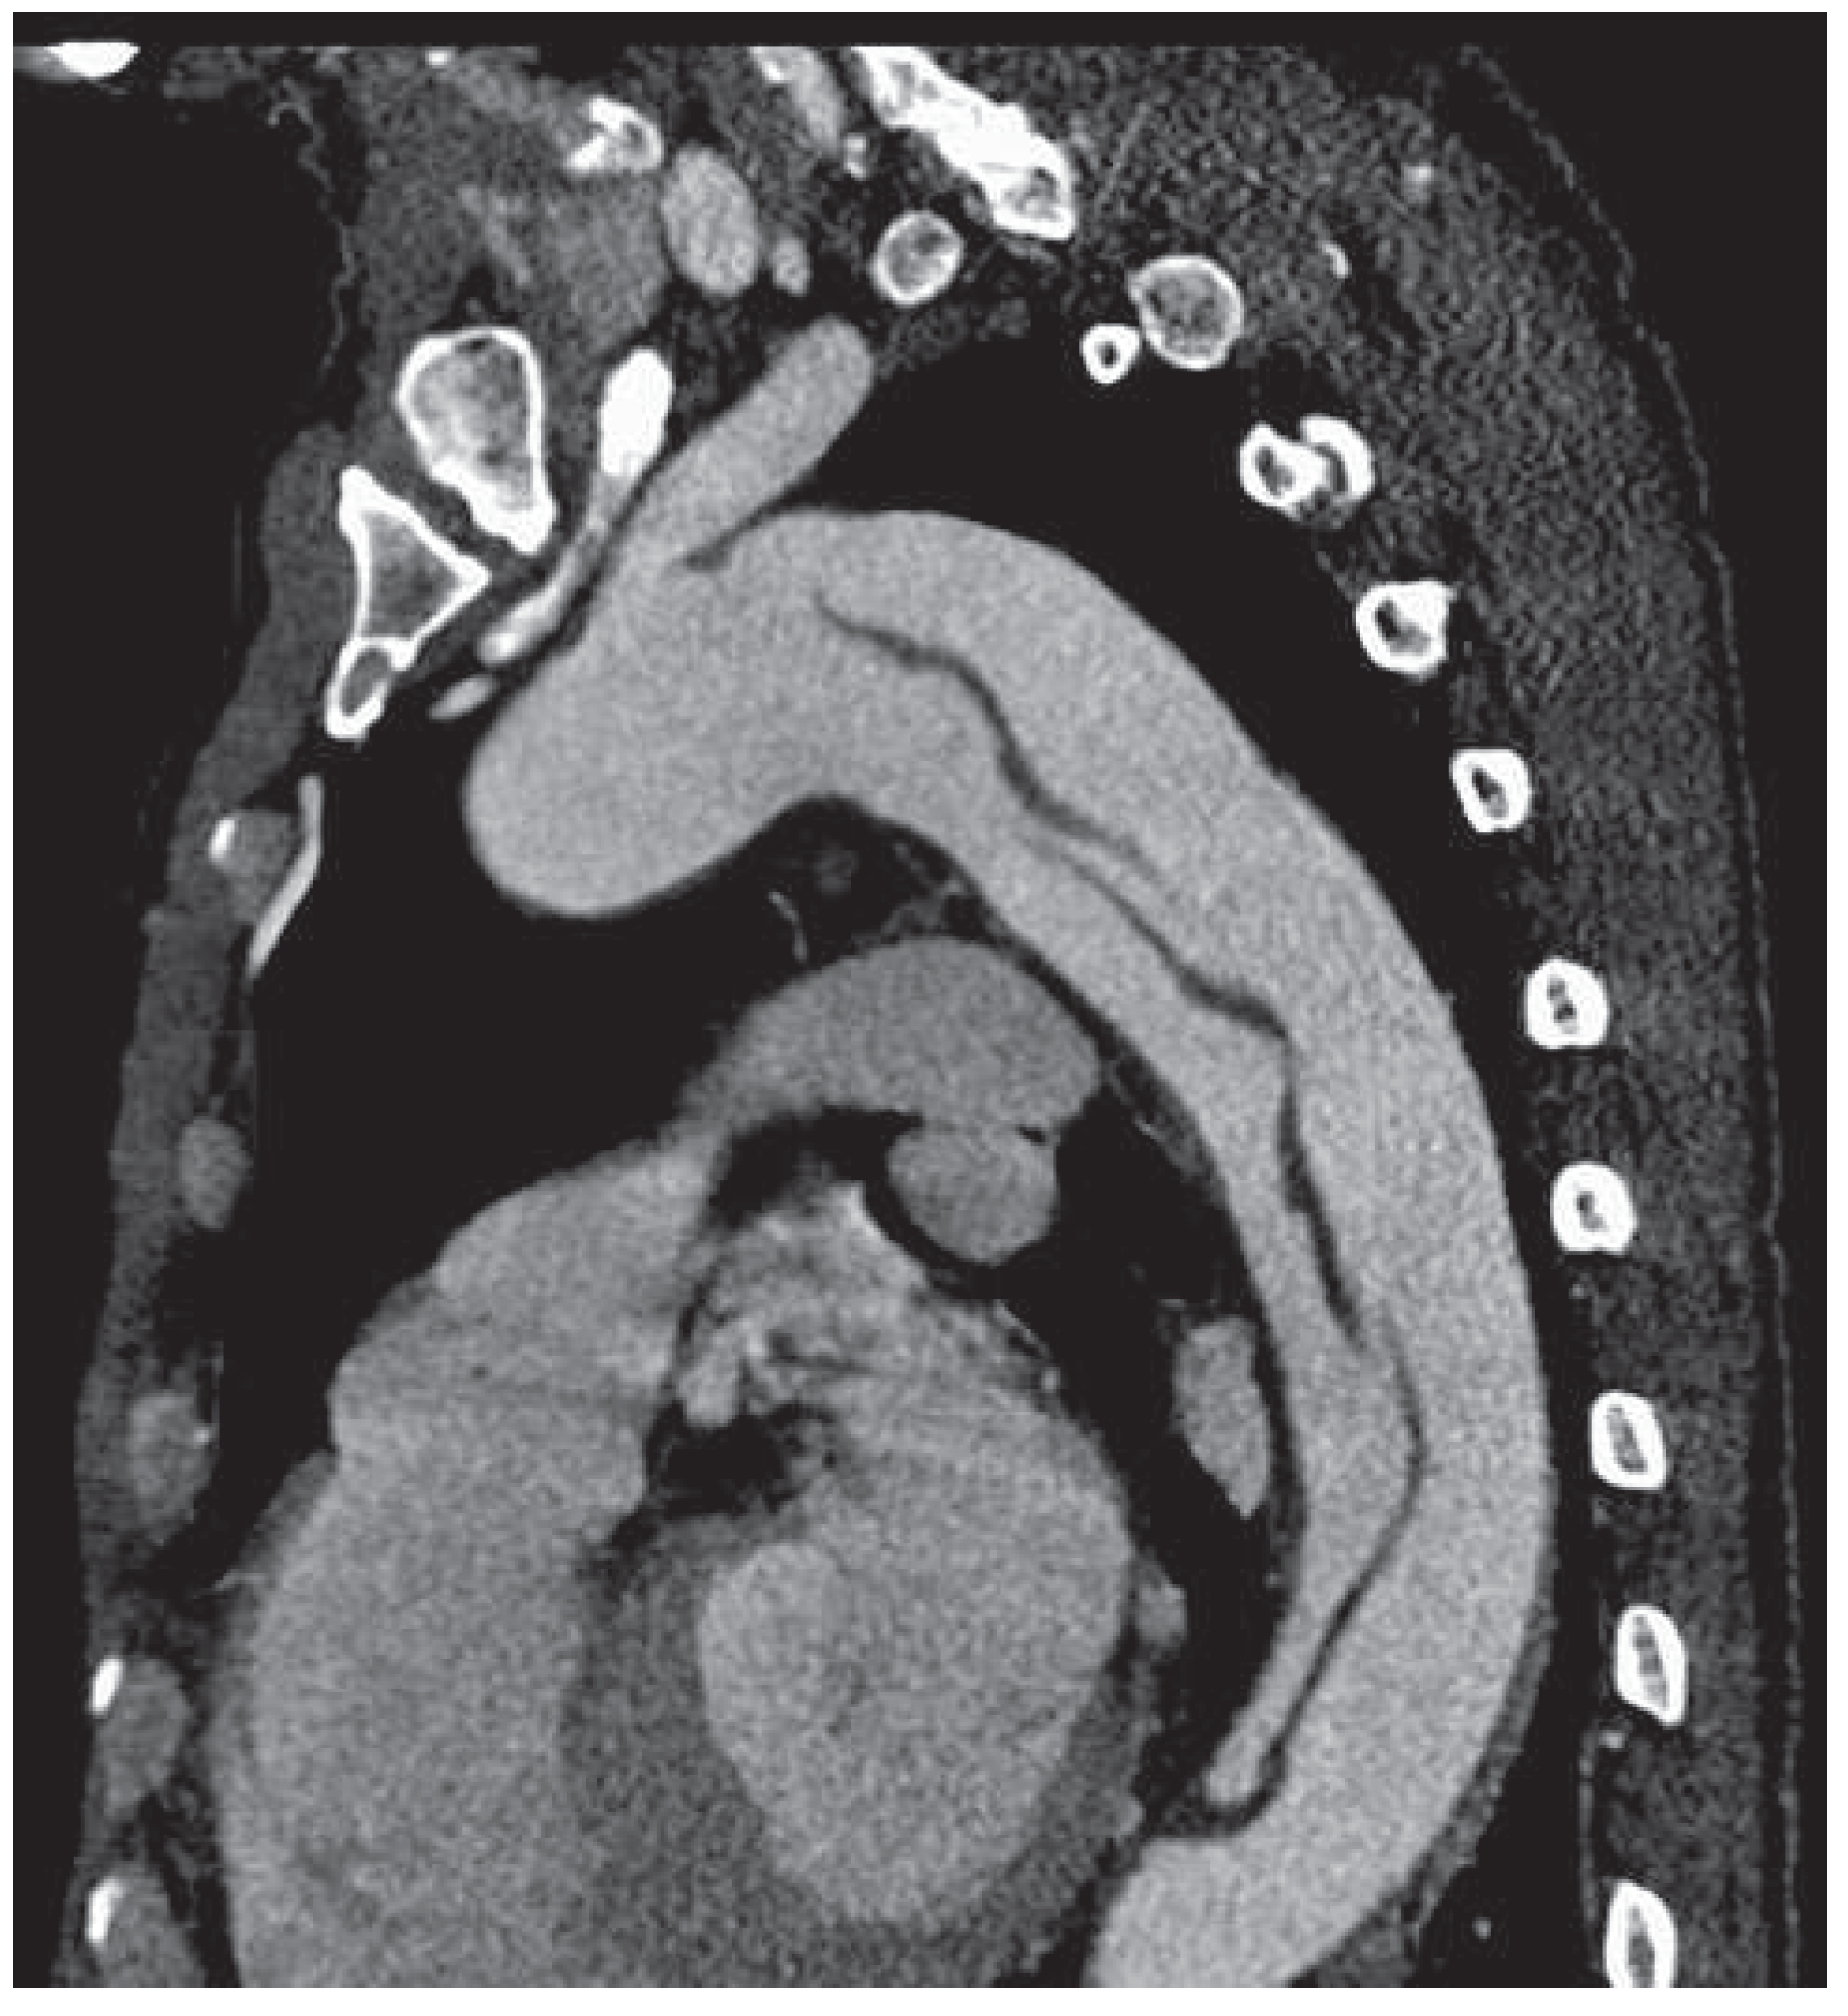

Endovascular Treatment of a Complex Type B Aortic Dissection

Case report